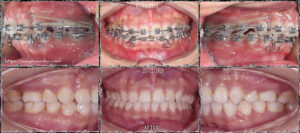

Bệnh nhân nữ, hô hàm trên & cười hở lợi. Môi trên mỏng, hớt, góc mô căm nhọn. Cung răng hàm dưới thiếu 1 răng cửa bẩm sinh.

Ảnh mặt nghiêng so sánh trước điều trị và sau điều trị: Đường viền mô mềm thay đổi rõ rệt, môi bớt nhọn, góc cằm môi được thay đổi trông thấy.

Kế hoạch điều trị: Nhổ 2 răng số 4 hàm trên, đóng khoảng bằng chun cuối, giải quyết khớp cắn sâu bằng cách đánh lún nhóm răng cửa và làm trồi nhóm răng hàm. Sử dụng T- loop SS 17×25 ở hàm dưới để đánh lún ở giai đoạn cuối.

Kết quả: khớp cắn ổn định, bênh nhân có một nụ cười hai hòa, thay đổi rõ rệt.